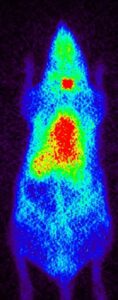

Just as it is possible to label a drug to find out whether it crosses the blood-brain barrier and then to measure the uptake and washout kinetics into the brain, it is also possible to use the labeled drug to measure uptake elsewhere. In this case the question is whether a drug reaches a fetus across the placental barrier. Reasons can include a desire to treat the fetus, or a desire to choose a drug partly on the basis of its exclusion from the fetus to minimize fetal toxicity and teratogenicity. These examples show selected images obtained from a study of live pregnant rats injected with I-124 labeled drug at 8, 11, 12 and 20 days of gestation. Injections were done at varying times, images shown are primarily of the abdomen only.

The “string of pearls” image of the fetuses is visible in the images. The rats had at least nine fetuses. From the whole-animal image at 8 days it is clear that this molecule did NOT accumulate well in the uterus or fetuses. The vast majority of administered dose was excreted. This can be a good result, of course. Further, uptake in this case appears to be in the placental areas and not in the uterine wall or contained within the fetuses.